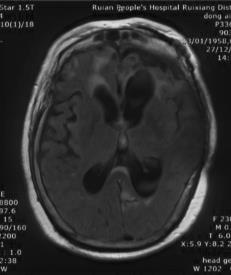

复阅2018年12月27日MRI片:左侧额颞部颅骨修补术后改变,两侧额颞叶、右侧小脑半球、左侧侧脑室后角旁均见长T1长T2异常信号,脑室系统扩大。提示左侧额颞部颅骨修补术后,两侧额颞叶、右侧小脑半球、左侧侧脑室后角旁软化灶形成。

图7-12,2018年12月27日MRI片,左侧额颞部颅骨修补术后,两侧额颞叶、右侧小脑半球、左侧侧脑室后角旁软化灶形成